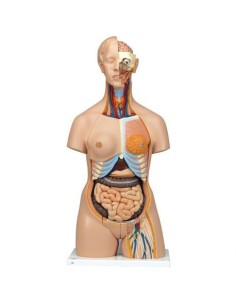

3B Scientifique, torse bisexuel japonais, décomposable en 18 parties B32/4